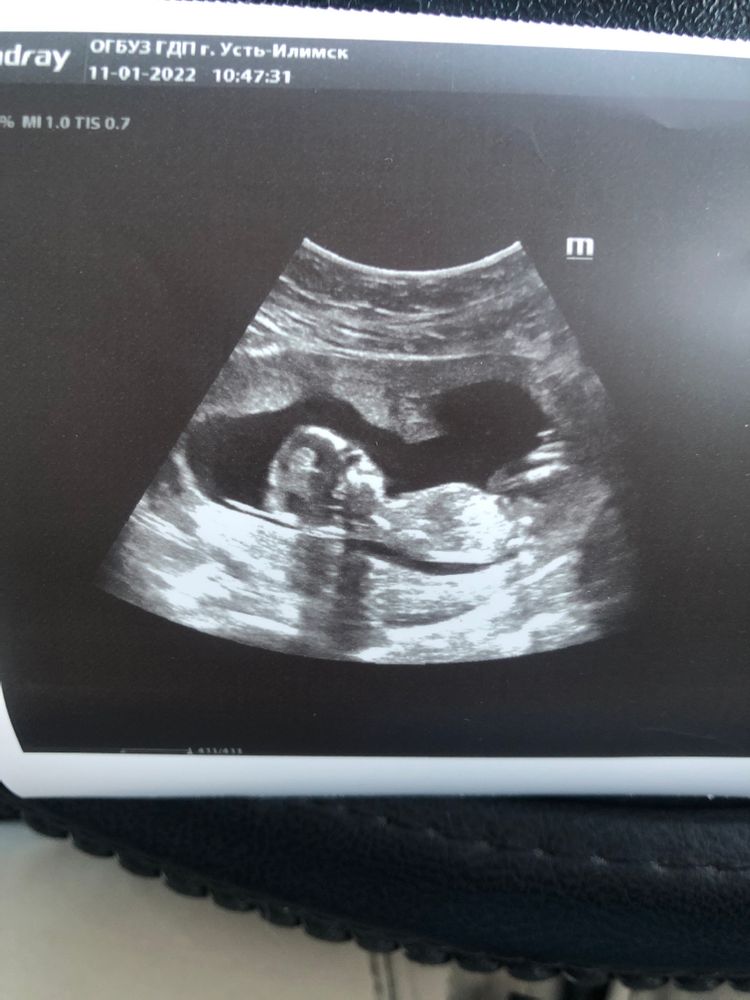

Как думаете, кто? 13 недель

В 13 недель уже бы точно видно было пипку))так мой врач узи сказал.Так что поздравляю,скорее девочка☺️🌟

Не вижу полового бугорка 🤔 чисто интуитивно, по форме головы - мальчик.

Лина, не думаю, что можно) Написала ж - интуитивно) Просто личное наблюдение - у мальчиков обычно лобики более выразительные, а девочки менее "лобастые", у них профили как бы аккуратнее. Ни разу не претендую на истину, просто наблюдение)

Девочка это

И нам предполагать сложно)) но у меня чуйка, что там мальчик )))

Марина, сначала врач сделал такое предположение, но потом забрал свои слова обратно) сказал не понятно все таки)